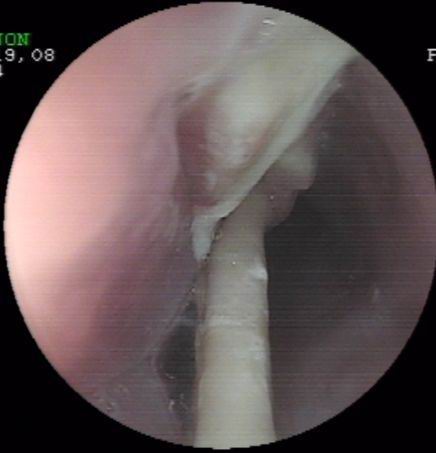

上個(gè)月末,一誤食異物(雞骨)胸骨后疼痛4天的患者經(jīng)胃鏡檢查確診為食管異物嵌頓。因患者異物嵌頓時(shí)間長(zhǎng),且患者其間還采取了其它一些清除異物的方法,造成異物的兩端均刺入食管壁,刺入處食管粘膜糜爛,充血,腫脹。按常規(guī),該患者應(yīng)收治外科行開(kāi)胸手術(shù)取出術(shù),但患者家境貧寒,且為家里主要?jiǎng)诹?,無(wú)法承受醫(yī)療費(fèi)用及開(kāi)胸術(shù)后所造成暫時(shí)的勞動(dòng)能力降低的損失。為減輕患者經(jīng)濟(jì)負(fù)擔(dān)及痛苦,在確診食管異物尚未造成食管周圍重要臟器損傷的情況下,該室決定在胃鏡下試取,經(jīng)多方面嘗試,最終成功將一長(zhǎng)約3.6cm兩端鋒利的雞骨(圖示)行內(nèi)鏡下取出,術(shù)后患者康復(fù)好,真正做到了微創(chuàng)手術(shù)解除患者大問(wèn)題,減輕了患者經(jīng)濟(jì)及軀體負(fù)擔(dān)。